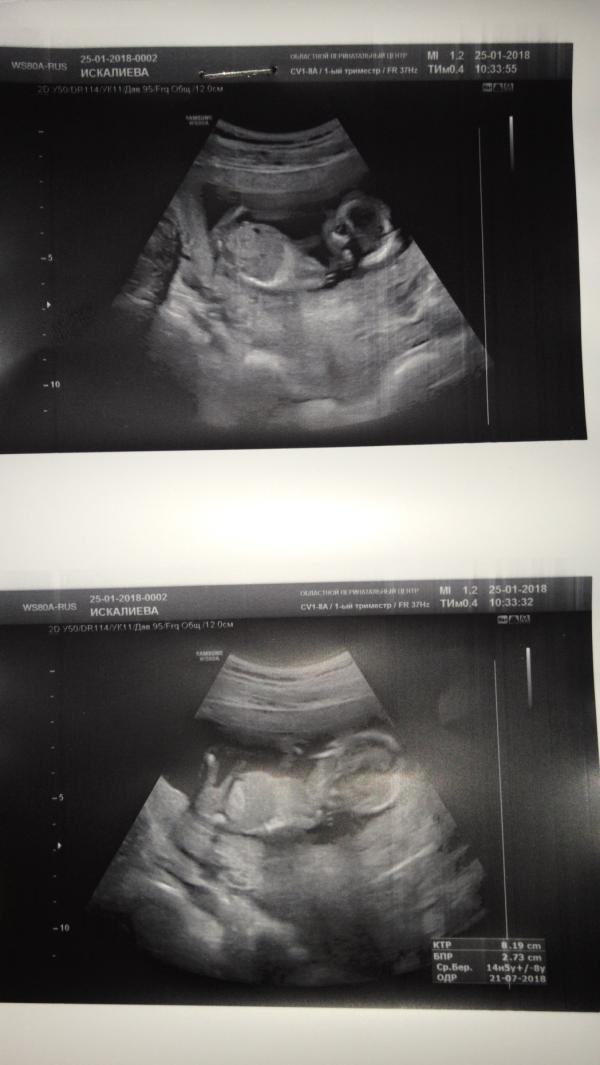

Не терпелось, сходила на узи узнать пол малыша, мне сказали что предворительно девочка, есть что то между ног но боюсь ошибиться возможно что и мальчиком окажется. Как так? На моём сроке не понятно? 😳хочу точно знать кто живёт у меня в животике, чтобы обращаться к нему как то. 😒

@zako-com, мне тоже на вашем сроке 16,5 недель (пошли с мужем, чтобы узнать пол😁) не могли определить и узнала только на 2м скрининге, на 20 неделе. Потерпите немного👐🏻

@km.dm.ss, сегодня ходила 16 нед 3 дня

@zako-com а вы на каком сроке были у узиста? Узи часто ошибается на первом скрининге. На Моего младшего сына говорили что девочка а я поверила и до второго скрининга разговаривала как с девочкой😂

@zako-com, не старое кажется дата написано 25 января 2018